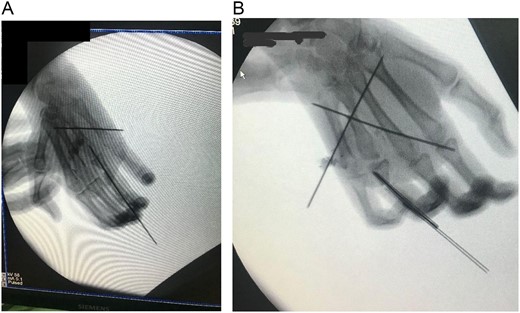

The metatarsal was fixed with the base of the metacarpal using Kirschner wire (K-wire) (Fig. 5A and B). An anastomosis was formed between the ulnar artery and the basilic vein. The artery was anastomosed with the common digital artery of the third web-space and two veins were anastomosed. A 1 deep vein was identified, and the other vein was anastomosed in the superficial venous system on the dorsum of the hand (Fig. 5A and B).

(A) Intraoperative X-ray showing K-wire inserted through the interphalangeal joint crossing the bone flap reaching up to the second metacarpal and another K wire inserted through the interphalangeal joints. (B) After fixation.